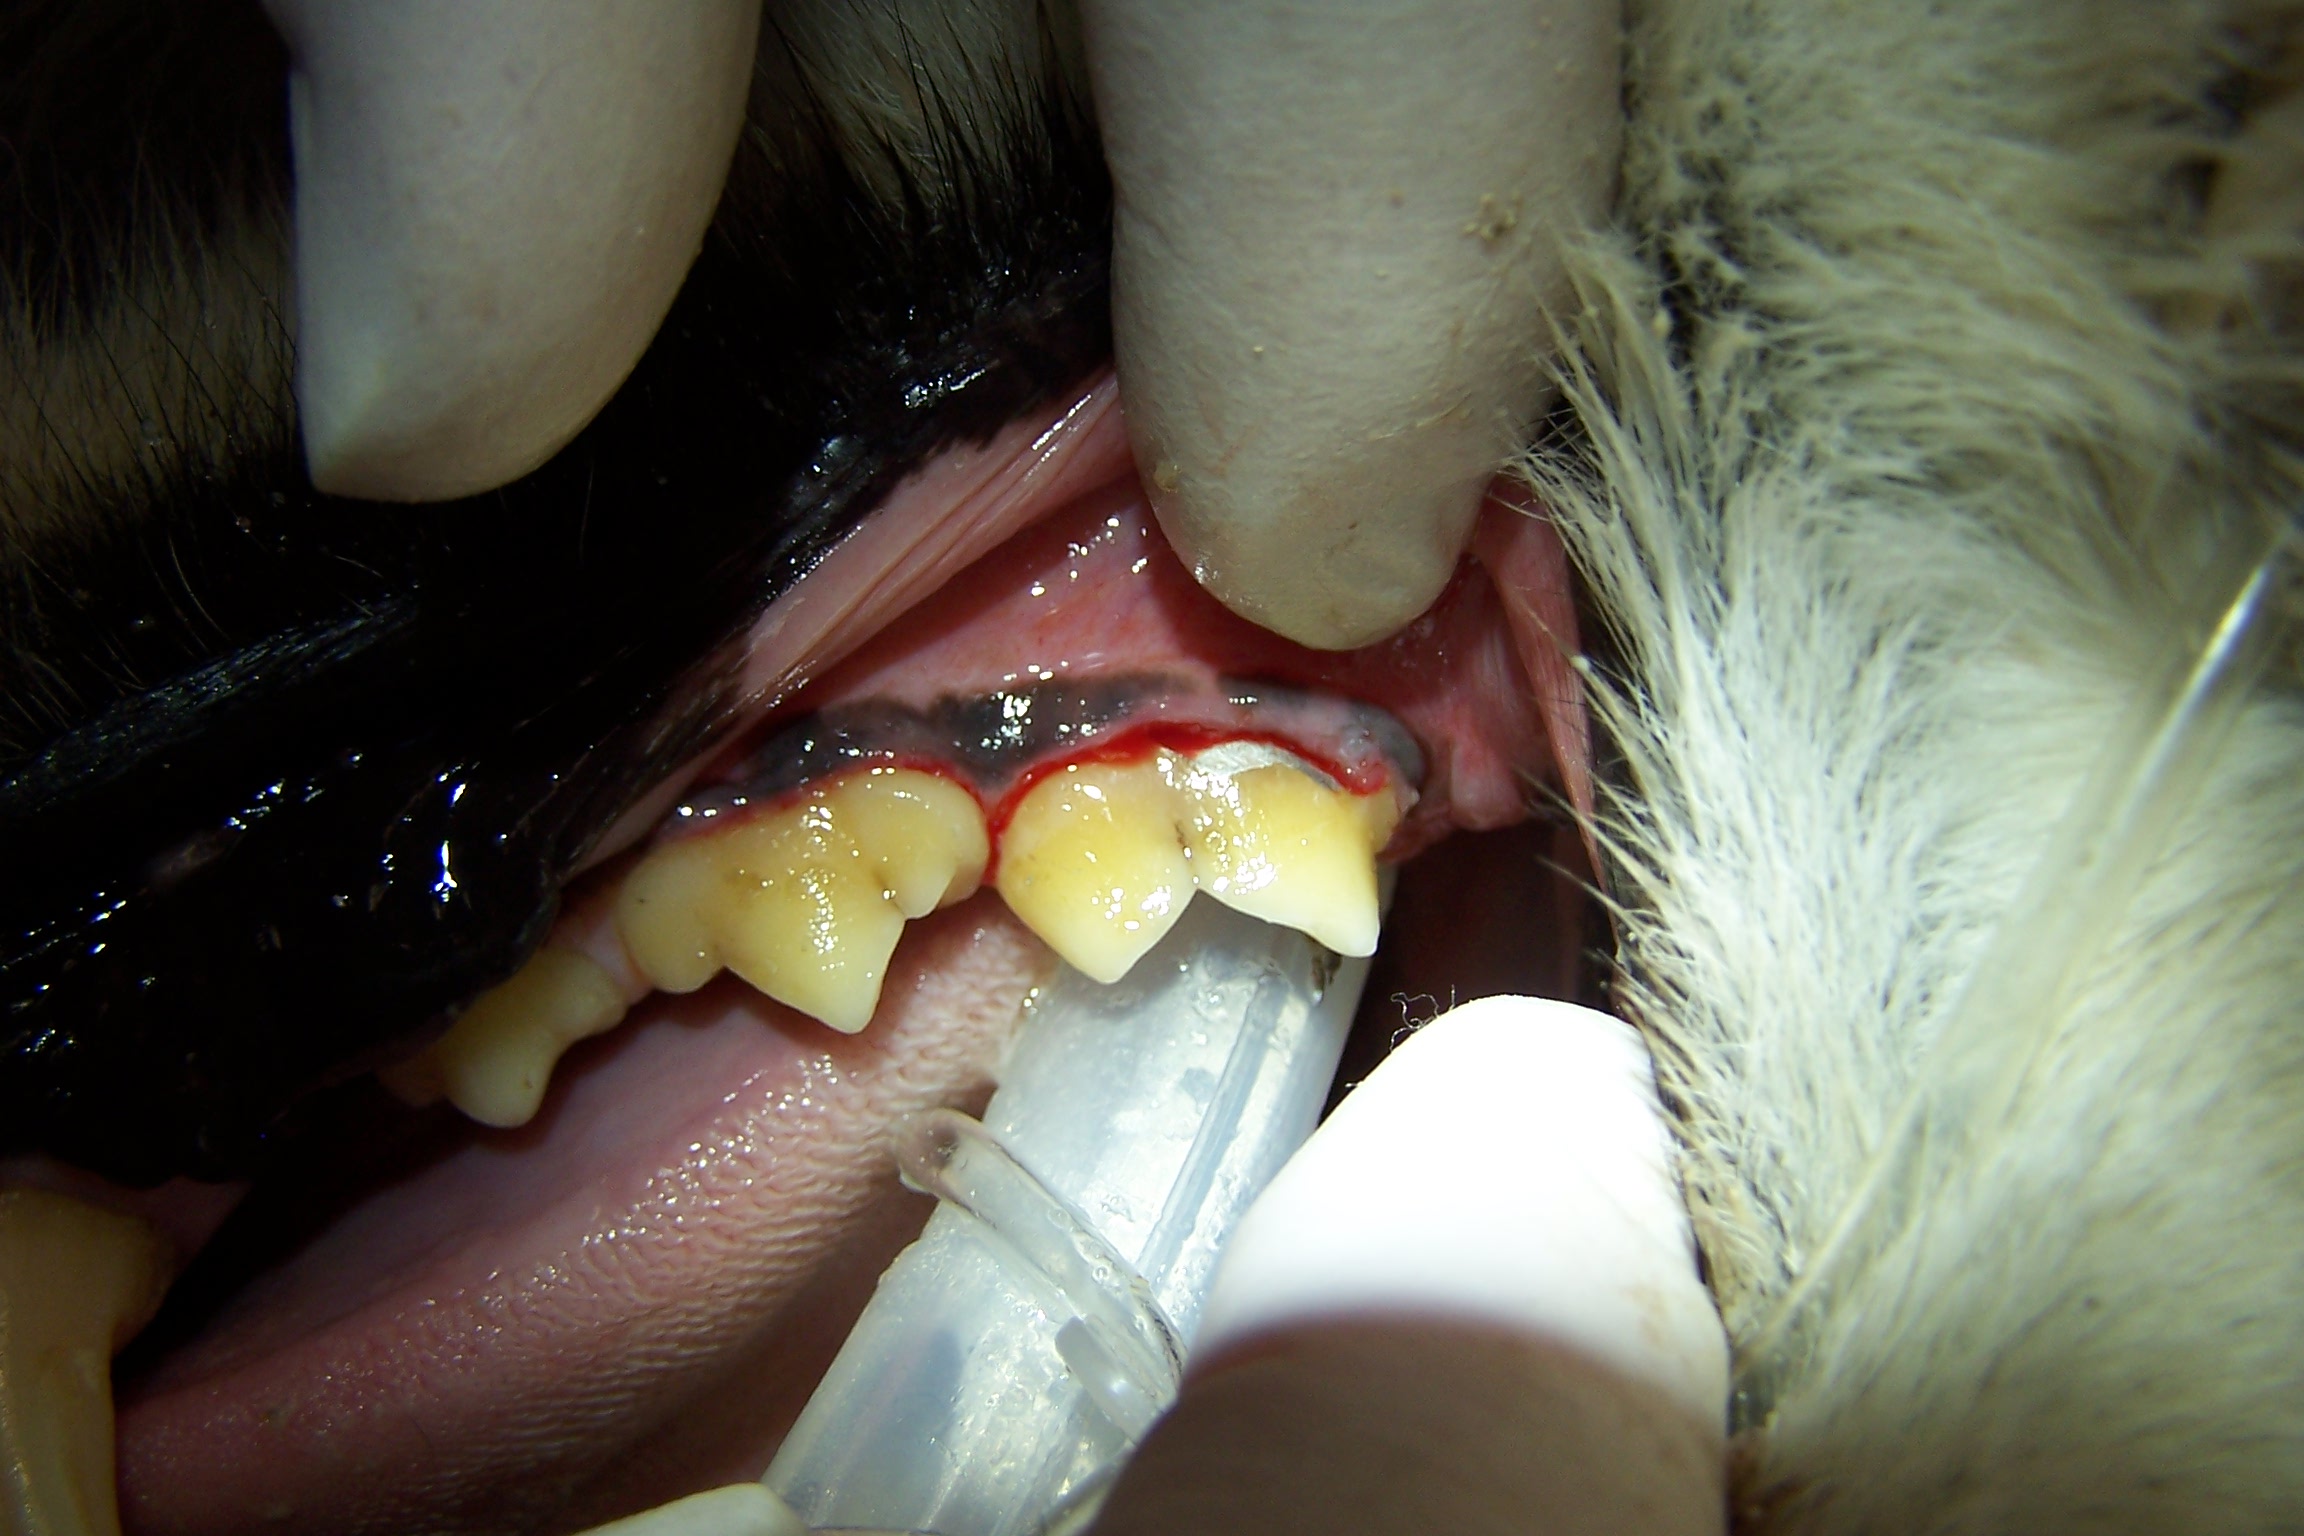

Feline Odontoclastic Resorptive Lesions

Felines exhibit a unique erosion at the cervical area called Feline Odontic Resorptive Lesions. These lesions appear to be associated with localized gingivitis. Many people have tried to explain why these lesions develop, however no one has come up with a definitive etiology.

I have restored FORL lesions with silver amalgam with excellent long term effect in multiple feline species. The lesions have ceased to enlarge. Restoration attempts with composite resin will fail, erosion will continue. Regrettably, most dentists and veterinary dentists will no longer have silver amalgam and the necessary instruments available to use it.

In personal conversations with Dr. Thomas Clark at Louisville Zoo I learned that he also has had success with silver amalgam. The lesion must be prepared with inverted cone burs to establish mechanical retention. These restorations have held up without failure for many years, see photos.